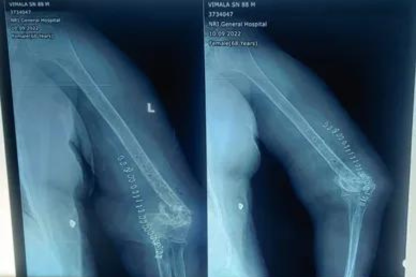

Nonunion (Bone hasn’t united)

Our hospital is specialized in treating nonunion cases where the bone hasn't united properly after a fracture. We use the latest orthopedic instruments and procedures to address these complex issues, ensuring optimal outcomes for patients.

Nonunion occurs when a fractured bone fails to heal properly. Treatment may involve revision surgery using advanced orthopedic instruments, bone grafting, or internal fixation techniques to help the bone heal correctly.